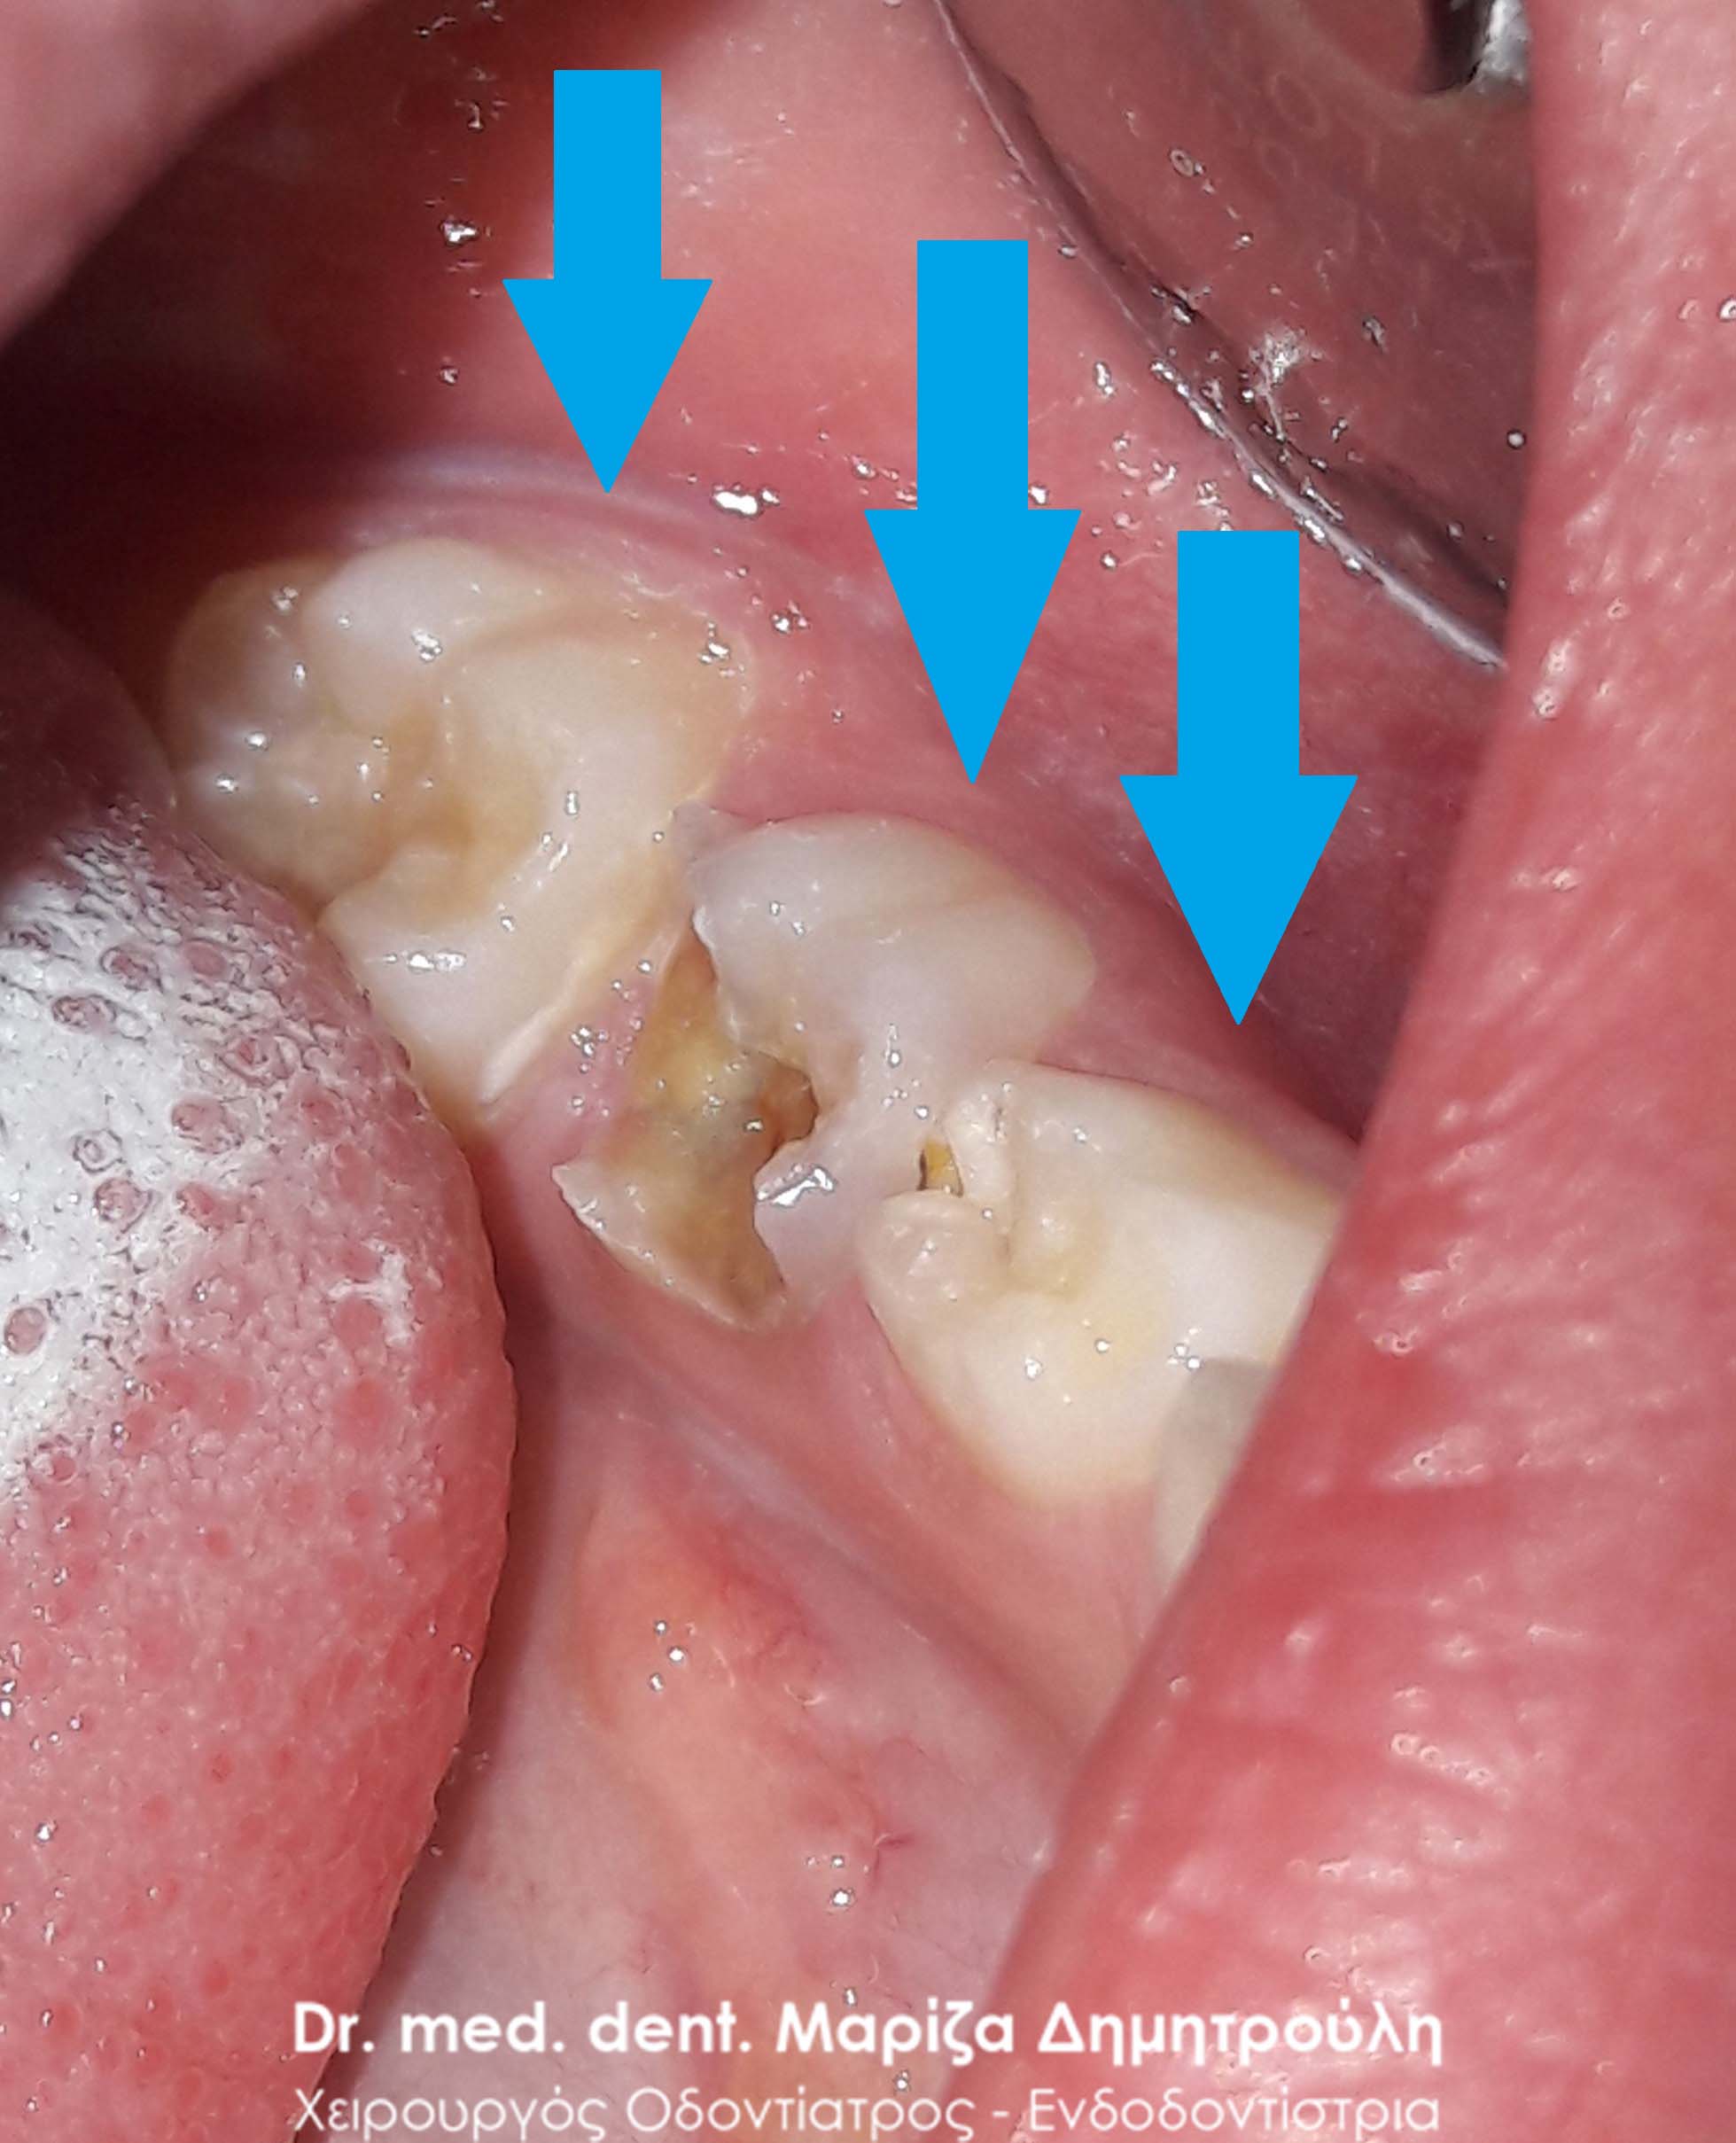

Dental fillings of primary teeth

Sealant and dental filling of primary tooth

BEFORE